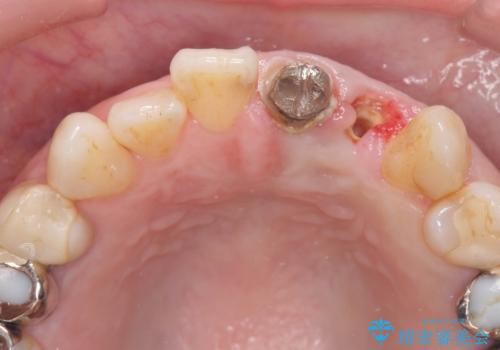

左上2は、クラウン メタルコアの除去を行ったところ虫歯の再発や亀裂を認め、長期的な予後の期待が難しいことから抜歯を行い

ブリッジで審美性の回復を行っていく運びとなりました。

精度、周囲の歯の色調にこだわったオールセラミックブリッジを作製し、しっかりと機能・審美性を改善することができました。